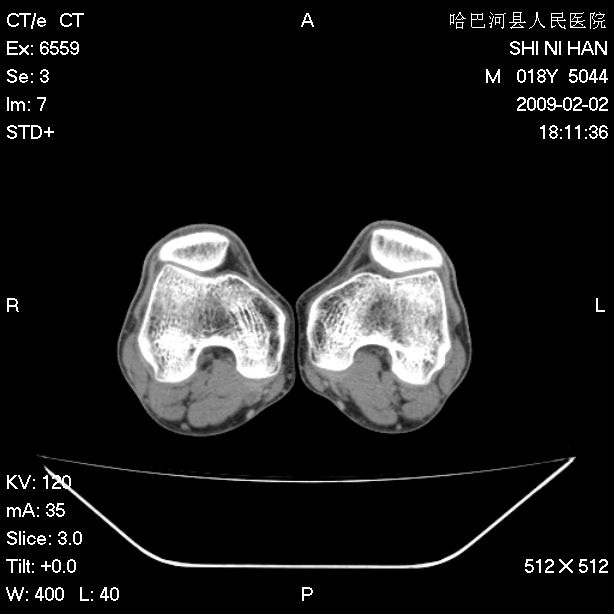

标题: CT17889:外伤后右膝关节反复疼痛3年余 [打印本页]

标题: CT17889:外伤后右膝关节反复疼痛3年余

ct未见明显异常。关节腔未见明显积液,半月板未见明显撕裂。但最好还是mri看看韧带及半月板情况。